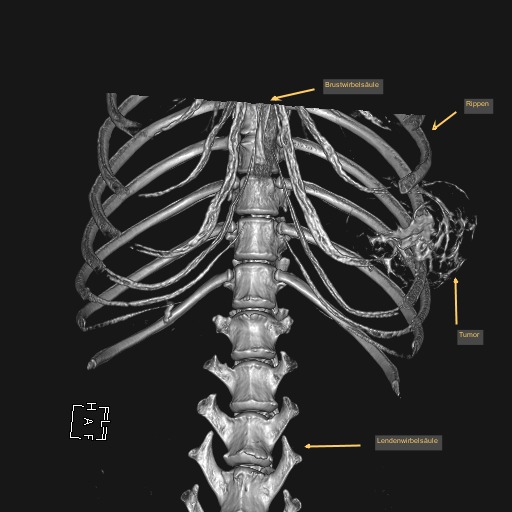

Leo wurde nun nach einer gründlichen allgemeinmedizinischen sowie labortechnischen Untersuchung zur Computertomographie (CT) angemeldet, die in Vollnarkose stattfinden muss. Mit dieser Technik werden mit Hilfe von Röntgenstrahlen ein Millimeter dünne Schichtaufnahmen angefertigt und damit das genaue Ausmaß des Tumors dargestellt. Zum anderen kann im Vergleich zu einem konventionellen Röntgenbild eine überlagerungsfreie Aussage über den Zustand des benachbarten Weichteilgewebes getroffen werden. Diese Informationen sind für den Chirurgen unumgänglich, damit er die Operation planen kann.

In diesem Fall wurde durch die CT das enorme Ausmaß der Umfangsvermehrung deutlich, sodass insgesamt drei Rippen inklusive der dazwischenliegenden Muskeln in Mitleidenschaft gezogen wurden. Die gute Nachricht war, dass der innerhalb der Bauchhöhle unmittelbar anliegende linke Leberlappen, Magen und Milz sowie der hintere Anteil des linken Lungenflügels im Brustkorb noch nicht vom Tumorwachstum erfasst waren.